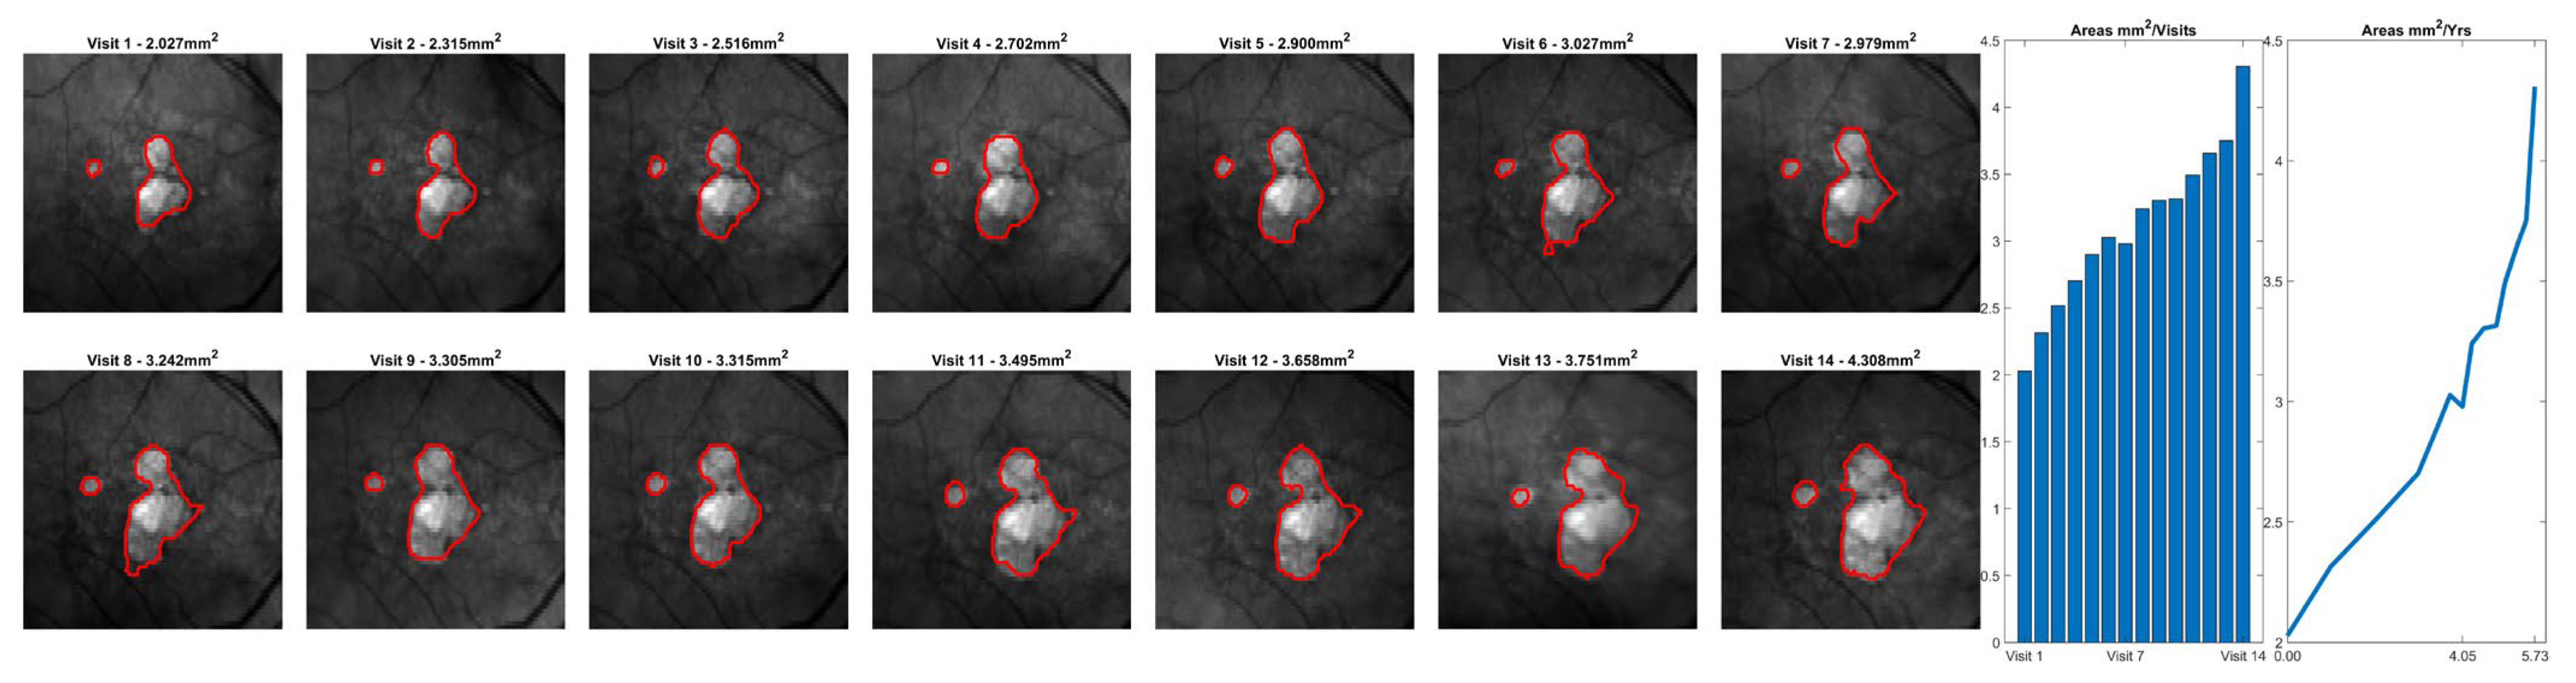

2.4. Analysis Methods

3. Results